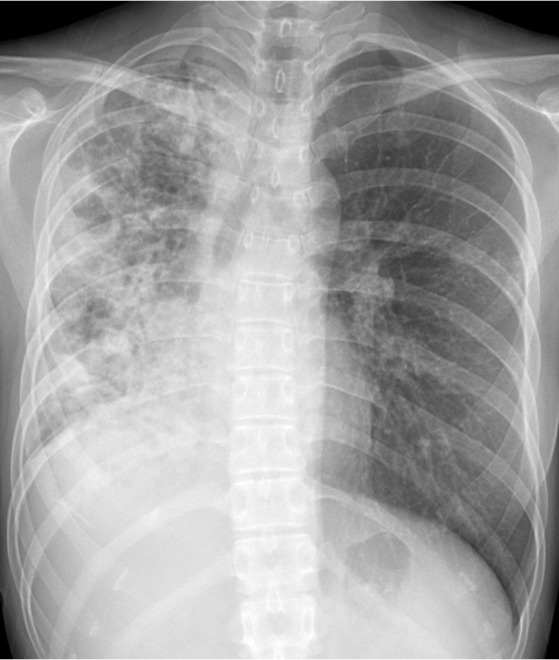

폐결핵 환자의 흉부 X-ray 사진

결핵의 진단을 위해서는 흉부 X-ray 검사가 일차적으로 권장됩니다. 그러면 당연하게도 환자에게 추가적인 검사 비용이 발생하는데, 대부분의 환자들은 검사 결과에 따라 이 비용의 성격을 다르게 받아들입니다. 실제로 결핵이라면 검사를 통해 질환을 잡아낼 수 있으므로 좋은 일이지만, 만약 결핵이 아니라 조금 오래가는 감기였다면 환자 입장에선 '헛 돈 썼다'는 인식을 갖기 십상이거든요. 실제로는 위험한 감염성 질환이 아님을 밝힌 것도 큰 소득이지만, 사람 마음이 별로 그렇게 작동하지는 않나 봅니다.